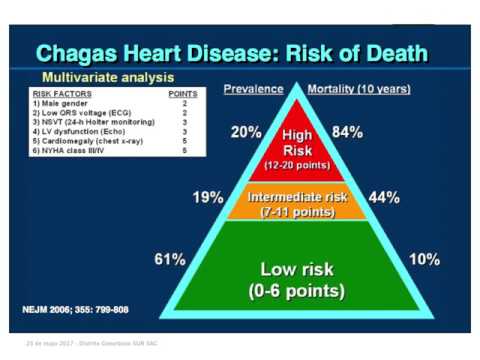

Enfermedad de Chagas 2017: después del BENEFIT. Parte 6/6

Enfermedad de Chagas 2017: después del BENEFIT. Parte 5/6

Enfermedad de Chagas 2017: después del BENEFIT. Parte 4/6

Enfermedad de Chagas 2017: después del BENEFIT. Parte 3/6

Enfermedad de Chagas 2017: después del BENEFIT. Parte 2/6

Enfermedad de Chagas 2017: después del BENEFIT. Parte 1/6